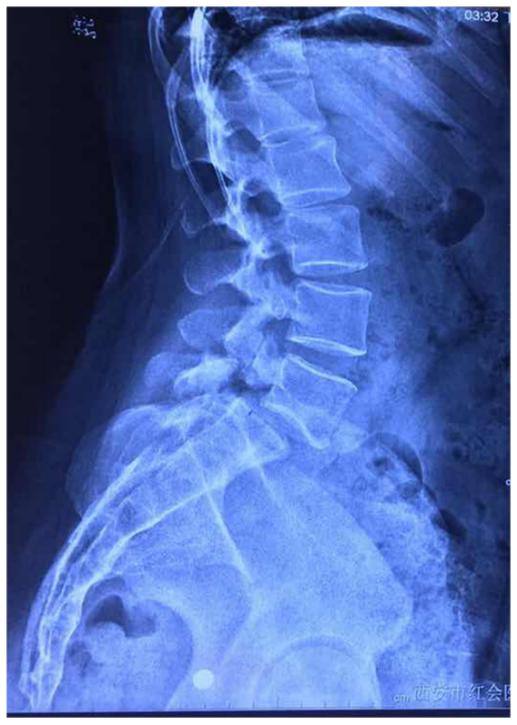

病例:峡部裂导致腰椎滑脱该怎么治疗?

图片尺寸517x725